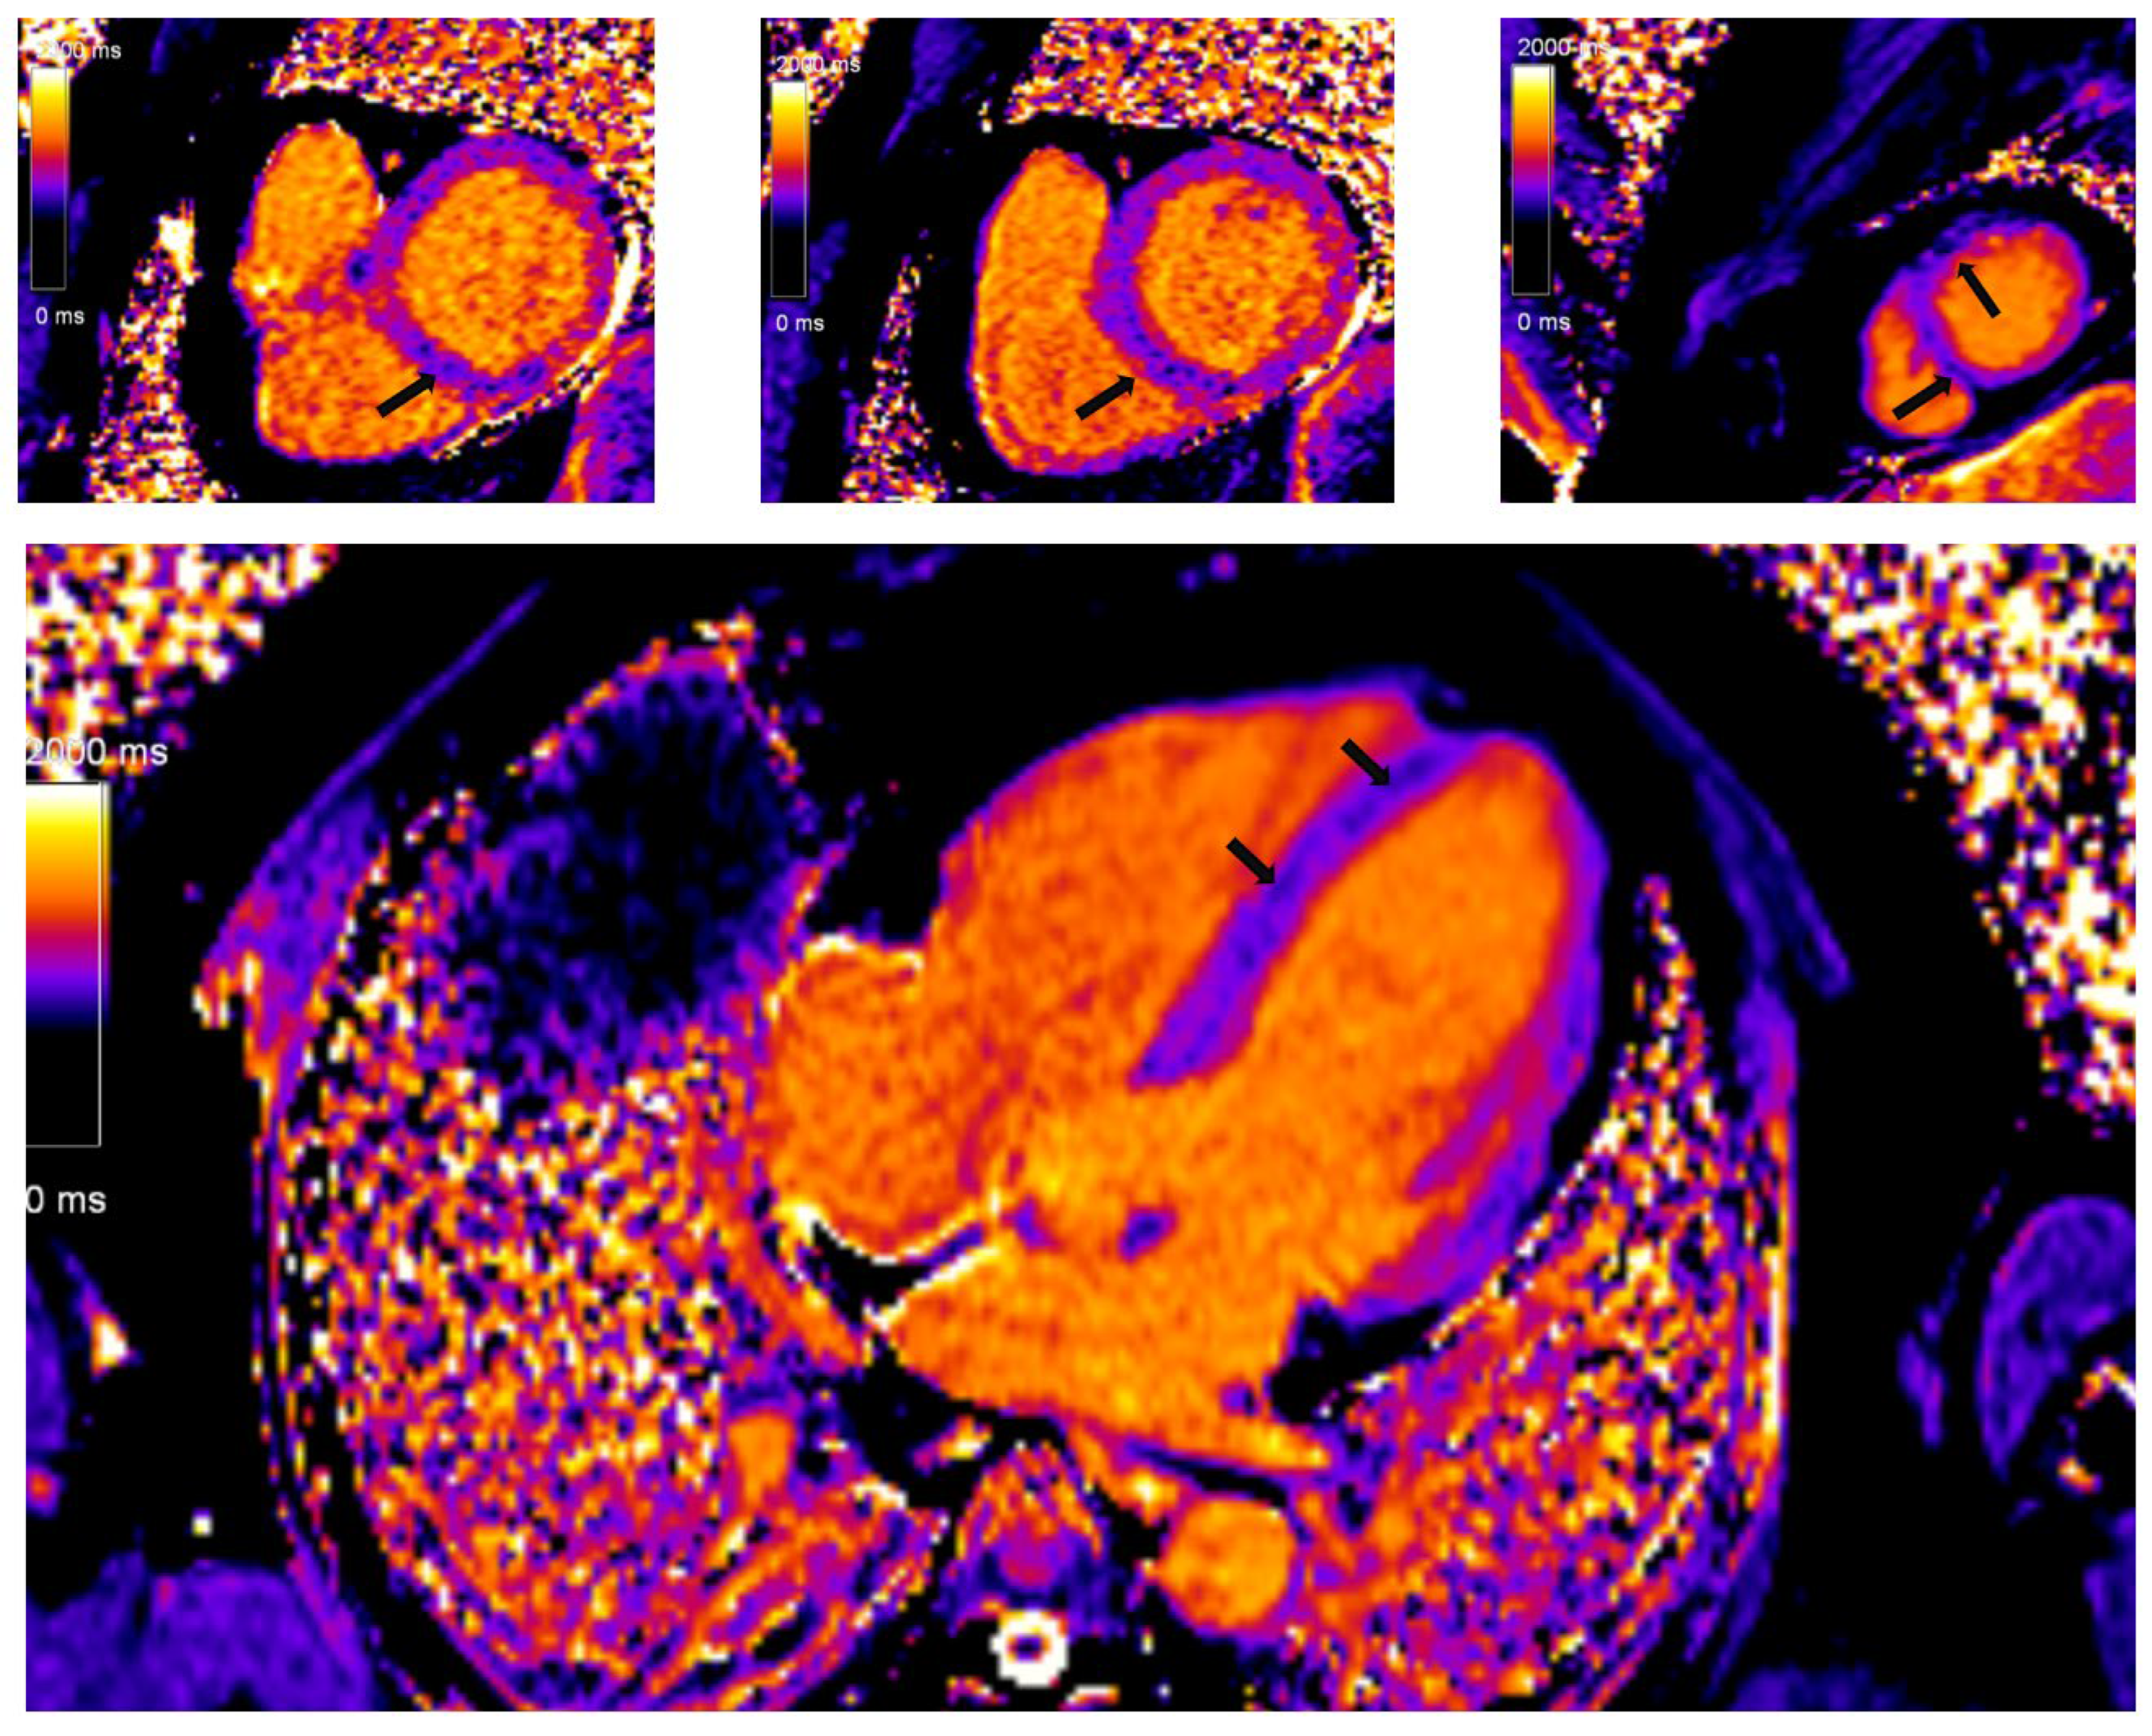

In recent years, with hardware and post-processing software improvements, predominantly driven by miltiparametric tissue mapping, the diagnosis and risk stratification of patients with CS has improved. Regional T2 mapping values are independent predictors of active myocardial inflammation in CS and may add additional discriminatory capability [79]. Prolonged or shortened native T1 time, both focally in the septum and globally, is a significant marker of the severity of the disease, while the fraction of extracelullar volume (ECV) is an independent predictor of future serious adverse events among patients with CS (Figure 4) [80]. The ECV esimation is also important in differentiation of other cardiac conditions, predominanlty myocarditis. It is important to note that CS patients had higher ECV values in the areas with LGE phenomenon in comparison to patients with myocarditis.

Figure 4. Myocardial tissue mapping in a patient with cardiac sarcoidosis and high degree AV block: native T1 mapping revealing the areas of shortened native T1 time indicating myocardial fibrosis predominantly in the septum (Avanto MRI, Siemens Healthcare GmbH, Erlangen, Germany, 1.5T, CMR Lab University Clinical Hospital Center Bezanijska kosa, Belgrade, Serbia).